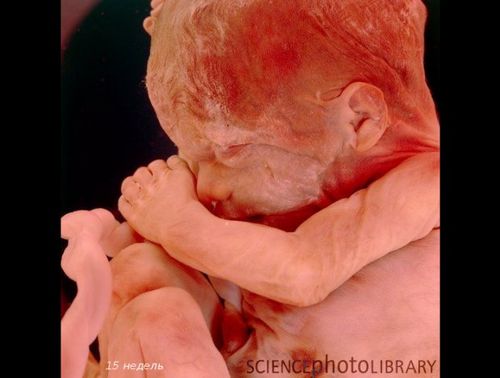

Уявіть, що ви тримаєте в руках картоплину. Ось такий довжини зараз ваш дитинка (

14 см при вазі 190-200 грам).

До 20-му тижні вагітності плід виріс до 25 см, виглядає як великий банан. Плід вже повністю сформований, а його тонка шкіра не настільки прозора.

У цей період відбувається знакова подія - дитина почує свою маму - биття її серця, дихання, голос (його окостенілі слухові кісточки тепер здатні проводити звуки). Малюк смокче пальчик, стає більш енергійним.

У кишечнику утворюється первородний кал - меконій і запускаються нирки. На очках чітко видно повіки і вії.